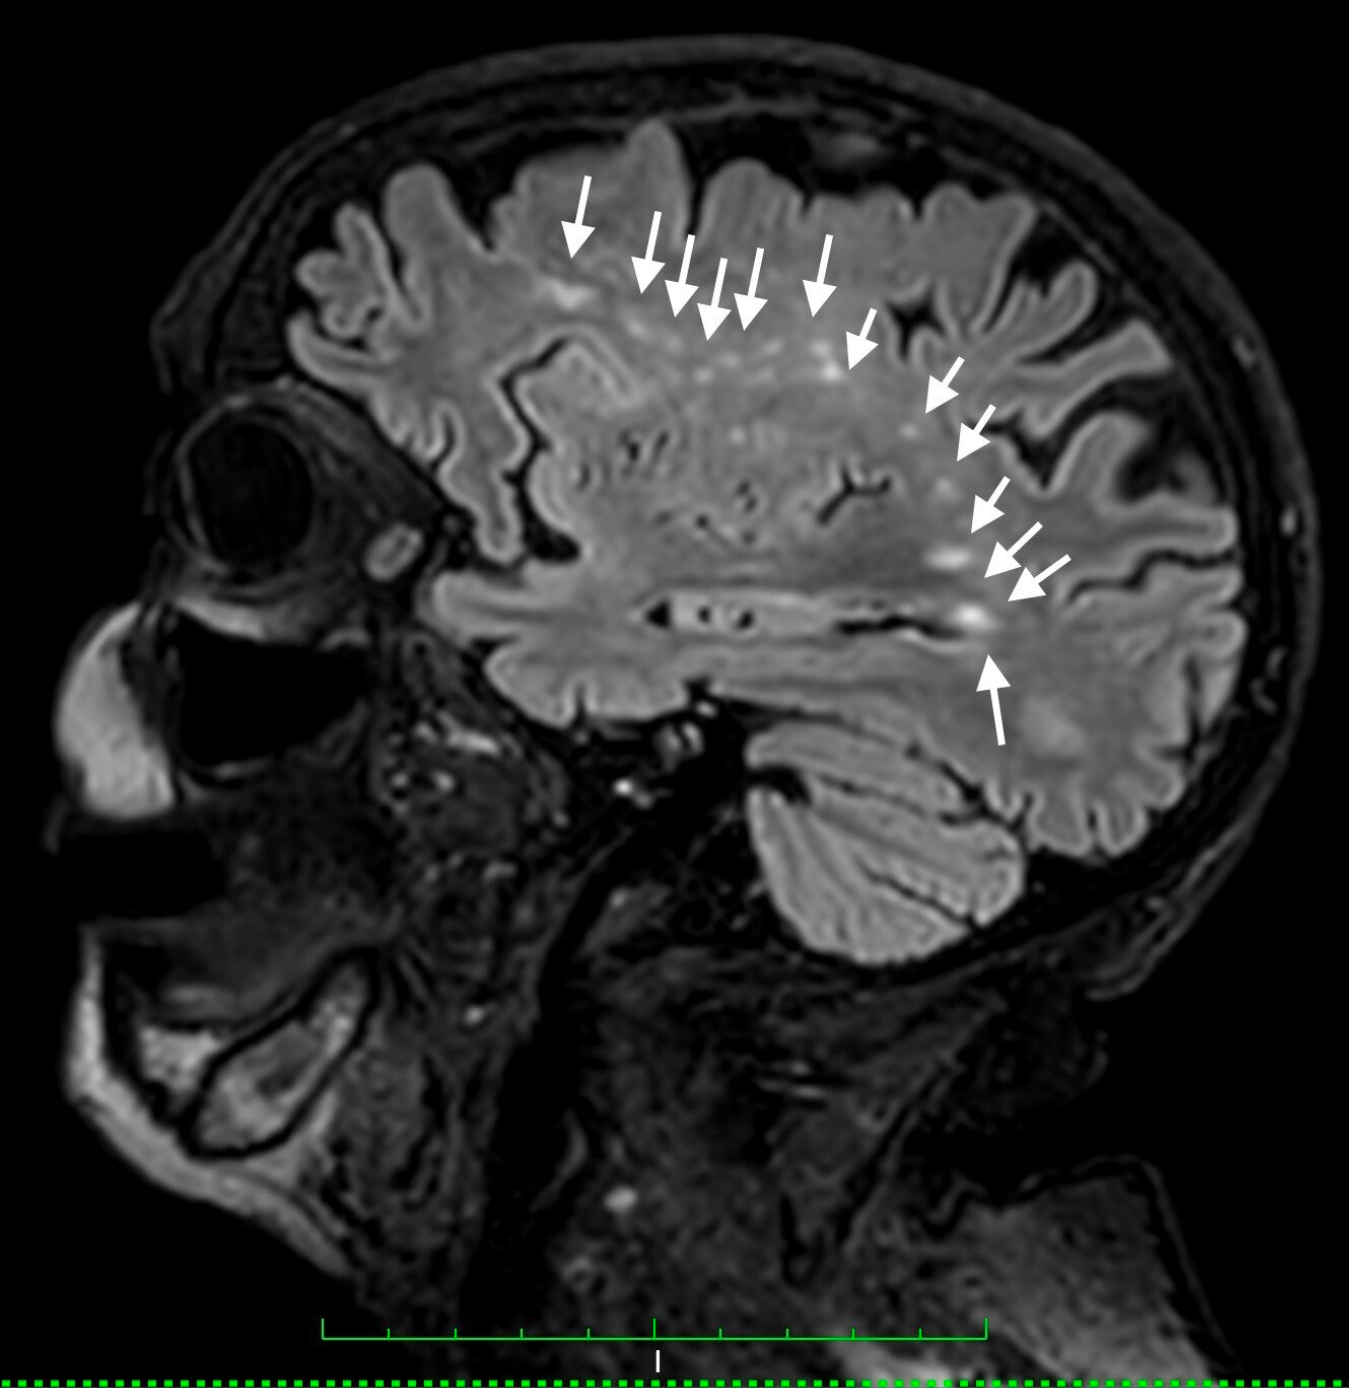

Since March 22nd, 2023, following the 3T MRI scan, a long journey with cysticercosis began, leading to a diagnosis and the correct initiation of albendazole treatment (400 mg b.i.d.). Either standard or increased doses, matching the maximum allowed (400 mg, two tablets t.i.d.), were prescribed, resulting in definitely positive clinical and imaging outcomes.

No farther than 19 months later, as of October 14th 2024, by directly tackling the responsible pathogen, the brain imaging (TC this time) appeared sufficiently normalised,  what's more corresponded by a perfect brain performance, completely regained from the previous assessment, when central neurological capability was affected (wake/sleep inversion, modified temper, paraparesis, and paraplegia),  and completely granting a normal, efficient, and functional relationship's life.

Such achievements were not solely reached through the pharmacological treatment undertaken, as detailed above. Indeed, a key factor was the establishment of prolonged—ideally continuous—hyperbaric oxygen therapy to counteract the anaerobic nature of cysticercal ova. This served as a fundamental adjunct—pivotal rather than merely additional—demonstrating early therapeutic efficacy, even though precise dosages, modalities, and breathing interfaces required further definition.